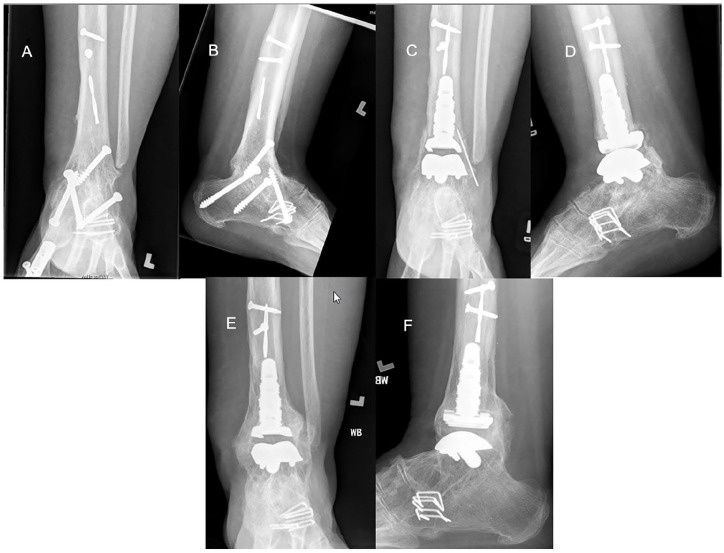

Methods: Between May 2010 and August 2019, 27 patients underwent conversion using a prosthesis with an intramedullary tibial component, 21 of which were available for the study. Six patients had a deficient distal fibula, and 5 were available for follow-up. Our primary outcome measure was having a total ankle arthroplasty in place. Secondary outcomes were evaluated postoperatively with a visual analog scale, the American Orthopaedic Foot & Ankle Society (AOFAS) ankle and hindfoot score, a satisfaction survey, and radiographic assessment of the arthroplasty and any concomitant hindfoot fusions.

Results: Mean follow-up for all patients was 7.6 (2.6-11.8) years, with follow-up of the deficient fibula group of 8.2 (4.9-11.8) years. Complications included malleolar fracture with or without subsequent surgery (n = 5), varus deformity (n = 1), and wound dehiscence or infection (n = 2). At final follow-up, all patients, including the 5 with a deficient distal fibula, had an intact ankle arthroplasty, although 3 with intact fibulas had undergone prosthetic revision. Postoperative dorsiflexion was 4.5 ± 5.1 degrees and plantarflexion 20.9 ± 13.37 degrees. There were no pseudarthroses in the 11 patients with concomitant hindfoot arthrodesis. Mean (±SD) VAS score was 4.4 ± 3.0 and AOFAS score was 71.2 ± 21.7. Sixty-seven percent reported that they were satisfied or very satisfied, with 16% dissatisfied or very dissatisfied. One of the deficient fibula patients was very dissatisfied. Seventy-six percent had no limitations with activities of daily living and two-thirds of those had no limitations at all.